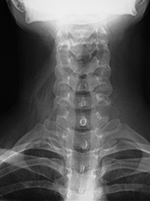

Normal everyday items carried or worn by patients - eyeglasses, earrings, hearing aids, and jewelry - may be mistaken for a medical device or foreign body; or, they may interfere with radiographic evaluation of the underlying soft tissue and bony structures. Earrings often show up on head and neck radiographs. They usually cause no confusion, but at times they can resemble electronic apparatus or even cervical spine fixation apparatus (figure: earrings). The combination of frontal and lateral views help to correctly identify earrings from medical apparatus. Even if there are frontal and lateral views, it may be difficult to distinguish unusual earrings from hearing aids.

| Earrings: lateral view |

Earrings: AP view |

These earrings resemble cervical spine apparatus on the lateral view. |